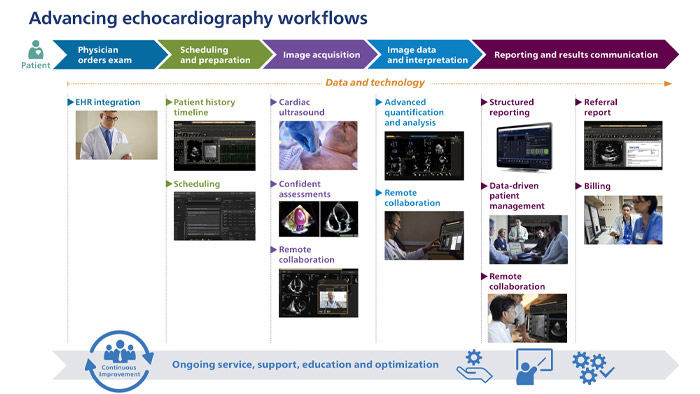

Workflow innovations. Process-based. People-driven.

See how Philips intelligence is enabling care teams to work with enhanced efficiency throughout echocardiography from the time a physician orders the exam to study completion, billing and referral.

Streamline cross-functional workflow and collaboration among care givers

This study assesses the clinical, operational, and economic benefits of Echo Workflow offering. Consensus was unanimous that the offering can enhance access to complete and longitudinal data needed for patient care decision-making; can lead to increased report consistency, measurement reproducibility and comparability; can help with better collaboration within the user's organization, can help with saving report turnaround time and with improving time-to-detection and/or diagnosis.